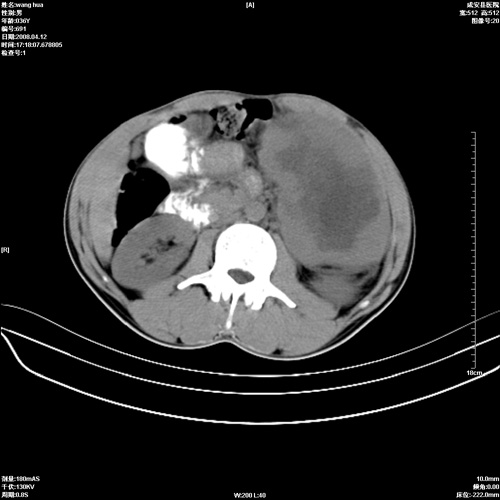

标题: CT12809:男36岁,自感上腹胀5天,B超诊断为脾肾之间占位,血 [打印本页]

标题: CT12809:男36岁,自感上腹胀5天,B超诊断为脾肾之间占位,血

请各位老师先分析一下定位 明天做增强

确实需要强化!先大胆预测一下,来源于脾脏的占位,血管瘤或淋巴瘤可能性大。

脾脏明显增大,其内见巨大低密度灶,境界不清,病史较短,考虑恶性病变脾血管内皮细胞肉瘤可能。建议增强扫描与脾脏淋巴瘤及血管瘤鉴别。